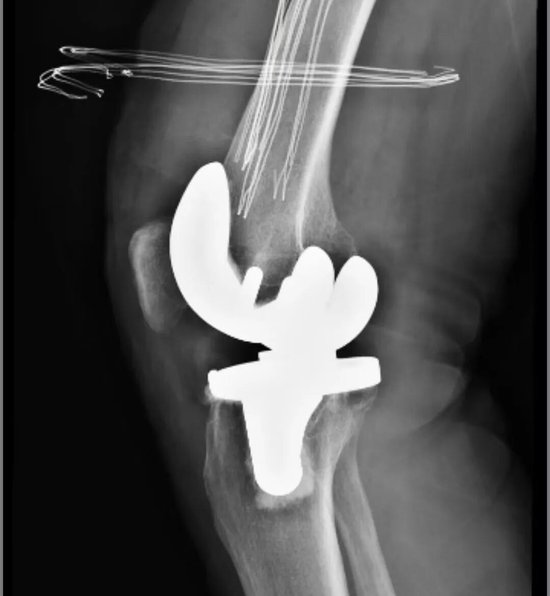

经关节外科门诊系统检查,发现患者右膝关节内翻畸形3°,屈伸活动范围仅10-110°,关节功能严重受限,伴有右膝关节骨性关节炎。为确保手术安全与效果,科室团队秉持严谨态度,为其安排了全面、系统的术前评估。在综合研判其整体健康状况,并确认心肺功能良好、各项指标均符合手术要求后,团队为其量身制定了个性化、精准化的手术治疗方案。

手术在腰硬联合麻醉下进行,由经验丰富的杜明主任主刀,倪守洋医生担任助手。术中探查发现,患者关节滑膜增生水肿,关节软骨已达IV度退变(最严重等级),软骨下骨裸露,边缘骨质增生显著。这对手术团队的病变清理精度、假体安放角度及软组织平衡技术提出了极高要求。

杜主任凭借丰富的经验和娴熟的技术,精准切除了病变的滑膜与增生骨赘,在有限的解剖空间内,成功为患者安装了型号匹配的胫骨与股骨假体。术中即时测试显示,膝关节屈伸活动度可达120度,假体位置精准、稳定性优异,手术顺利完成。